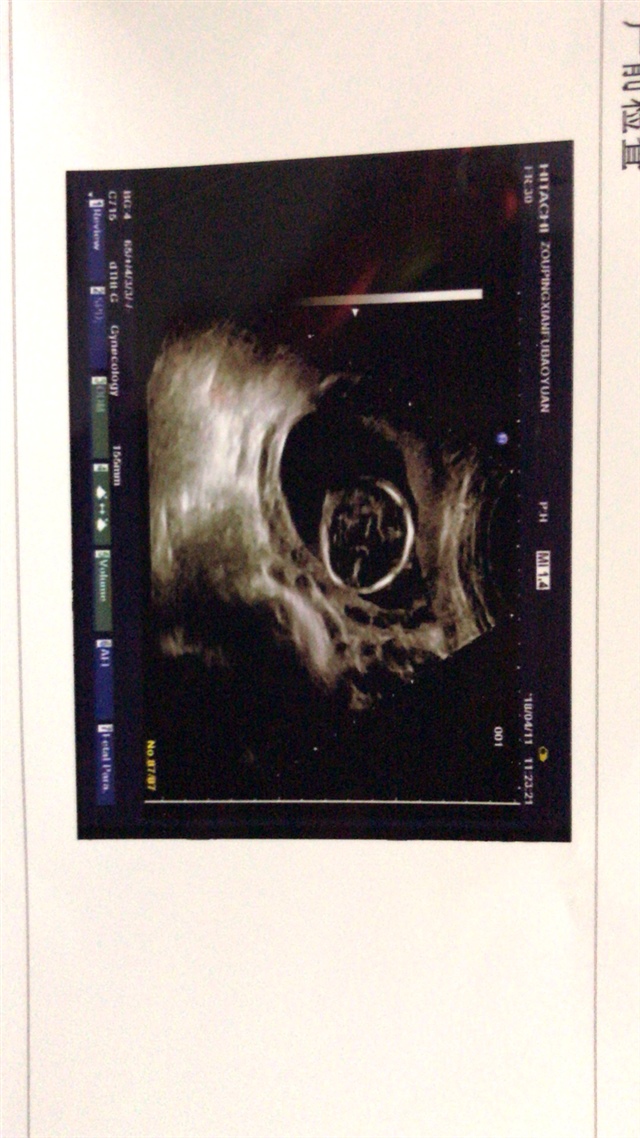

男

赵颖[帖主]:亲,你是怎么看出来的

oreo:神仙了,双顶径bc可以看男女